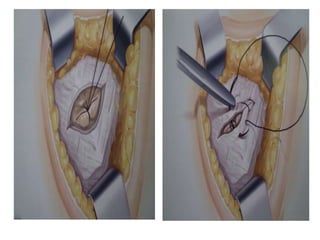

 Cuando existe saco

herniario: apertura del

saco, reducción del

contenido, cierre del

peritoneo y sutura del

defecto fascial.